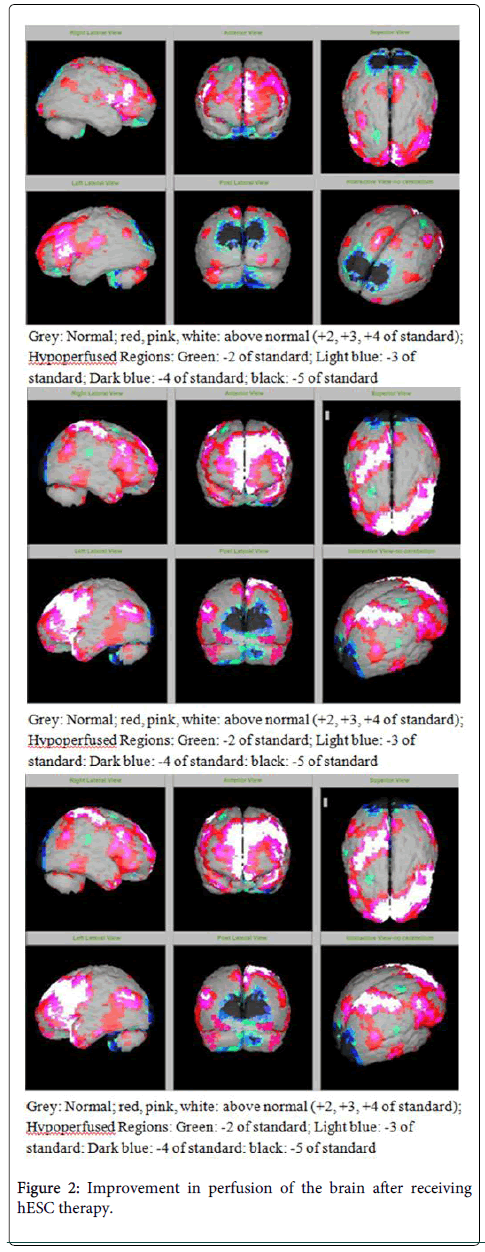

圖1:接受hESC治療前大腦灌注的改善。

該患者的SPECT掃描如圖1和2所示。

SPECT掃描

在研究開(kāi)始和結束時(shí),23名患者接受了SPECT掃描。在枕葉或額葉或雙葉中觀(guān)察到灌注不足。23例接受SPECT掃描的患者中,5例患者表現為枕葉灌注不足,7例患者表現為額葉灌注不足,11例患者表現為枕葉和額葉灌注不足。

總體而言,治療結束時(shí),2名患者的灌注正常,18名患者(12名男性和6名女性患者)顯示灌注顯著(zhù)改善(>60%),3名患者顯示灌注中度改善(30-60%)。大多數在接受hESC治療前額葉和枕葉嚴重低灌注的患者在接受 hESC 治療后情況有所改善。23名可獲得SPECT掃描報告的患者的GMFCS評分在hESC治療后有所改善(表2)。

眾所周知,神經(jīng)干細胞可以通過(guò)重新填充受損區域并防止細胞進(jìn)一步退化來(lái)恢復正常視力。hESC通過(guò)增殖成相似的細胞類(lèi)型來(lái)啟動(dòng)受損細胞的再生。在本研究中觀(guān)察到灌注改善,這反映在SPECT掃描中。詹森等人研究顯示,一名5歲腦癱患者在接受臍帶血干細胞治療2個(gè)月后視力有所改善。